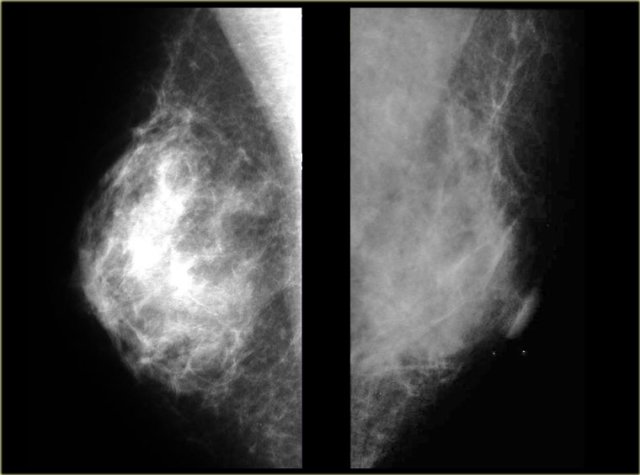

On the left two cases, that demonstrate, that it can be difficult to differentiate gynecomastia from carcinoma on a mammogram.

The carcinoma on the right is a little bit more encapsulated than the gynecomastia on the right.

In less than 10% of the cases a biopsy can be needed to make the differentiation.

On the left two more cases.

On the far left there is diffuse gynecomastia.

On the right a huge cancer which is encapsulated.

The last cases on the left look very similar to each other.

Based on the mammogram these two can not be differentiated.

In those rare instances a biopsy is needed.